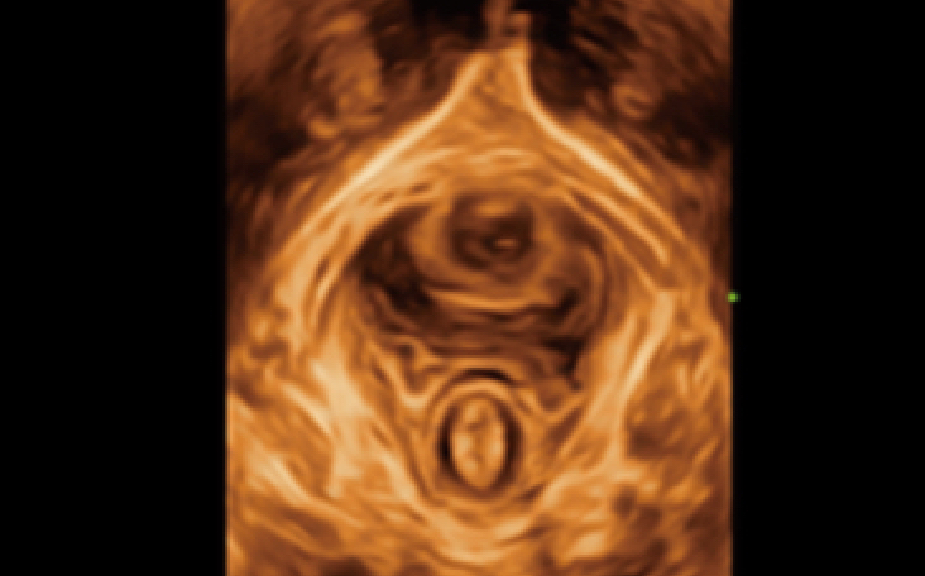

Innovadora mediciĂłn automĂĄtica 2D Graf

MĂ©todo Graf:

El mĂ©todo mĂĄs utilizado para la evaluaciĂłn de la cadera, los resultados corresponden a una clasificaciĂłn clara de la cadera. La detecciĂłn de estructuras clave se basa en algoritmos de aprendizaje profundo. Medida automĂĄtica (α y ÎČ) y clasificaciĂłn.

Simple y eficiente:

Mejore en gran medida la eficiencia del examen con un solo clic.

Preciso y confiable:

El sistema juzgarå si la sección es eståndar o no antes del cålculo, y también se permite el ajuste manual.